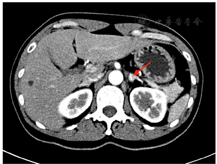

辅助检查:LH 1.7 IU/L(正常参考范围7.7~58.5,下同)、FSH 4.1 IU/L(25.8~134.8)、催乳素544.0 mIU/L(131~647)、雌二醇137.0 pmol/L(<505)、孕激素0.9 nmol/L(<0.401)、睾酮(T)6.4 nmol/L(0.101~1.42)、硫酸脱氢表雄酮(DHEAS) 6.27 μmol/L(0.101~1.42)、质谱法T 4.713 ng/mL(0.02~0.45)、质谱法DHEAS 4.3 ng/mL(4.30~6)、质谱法雄烯二酮1.218 ng/mL(0.2~0.75);餐后2 h血糖9.5 mmol/L(<7.8)、餐后2 h胰岛素97.4 μU/mL、餐后2 h C肽12.5 ng/mL;三酰甘油1.95 mmol/L(<1.7);红细胞5.52×1012/L(3.8~5.10)、血红蛋白182 g/L(115~150);余尿粪常规、肝肾功能、电解质、离子浓度、出凝血、空腹血糖、糖化血红蛋白、骨密度、肿瘤标志物、甲状腺激素、生长激素、肾素-血管紧张素-醛固酮、肾上腺素、去甲肾上腺素、促肾上腺皮质激素及皮质醇昼夜节律等未见明显异常。骨密度提示骨质疏松(腰椎T-1.9、髋关节股骨颈T-2.5);经阴道及腹部超声及盆腔增强MRI均提示子宫多发肌瘤、左侧附件区实质占位,大小约2.8 cm×1.9 cm(图1);肾上腺增强CT提示左侧肾上腺小结节,大小约1.1 cm×0.9 cm,腺瘤机会大(图2)。